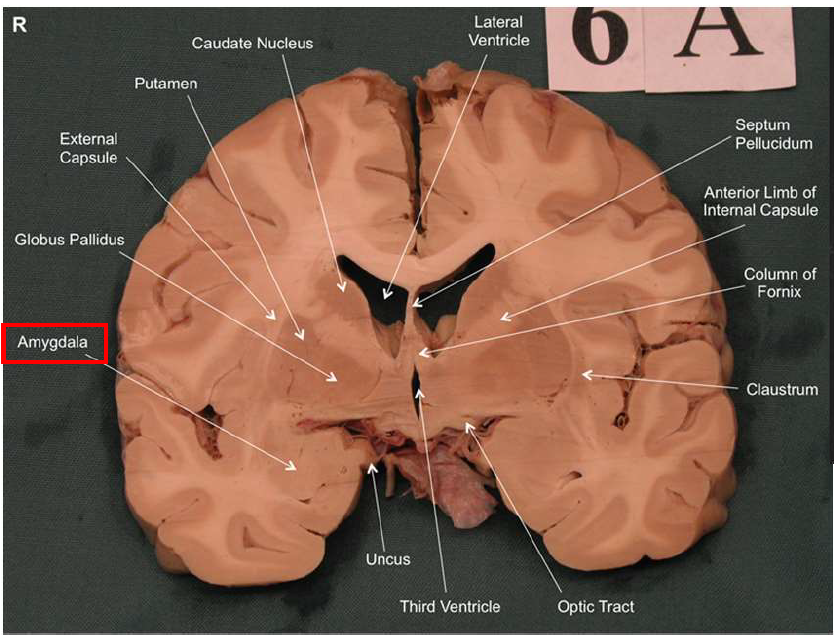

What is the function of the amygdala?

Emotions & Memory Hub

Processes emotions (esp. fear & pleasure)

Helps us remember emotional experiences

Imagine the amygdala as a fire alarm in your brain. When it senses danger (fire!), it triggers the alarm (fight-or-flight response) almost instantaneously and remembers the event vividly (emotional memory)

Stimulation of _ via the ipsilateral frontal cortex elicits aggression

amygdala

What is Kluver-Bucy syndrome?

Rare brain disorder caused by bilateral lesion of the amygdala. Due to lobectomies, encephalitis from Herpes simplex, stroke, or Alzhemier’s. Causes abnormal behaviors and memory problems:

Putting objects in mouth (hyperorality)

Excessive touching of objects (hypermetamorphosis)

Increased sex drive (hypersexuality)

Binge eating/purging (bulimia)

Difficulty recognizing objects (visual agnosia)

Memory problems (amnesia)